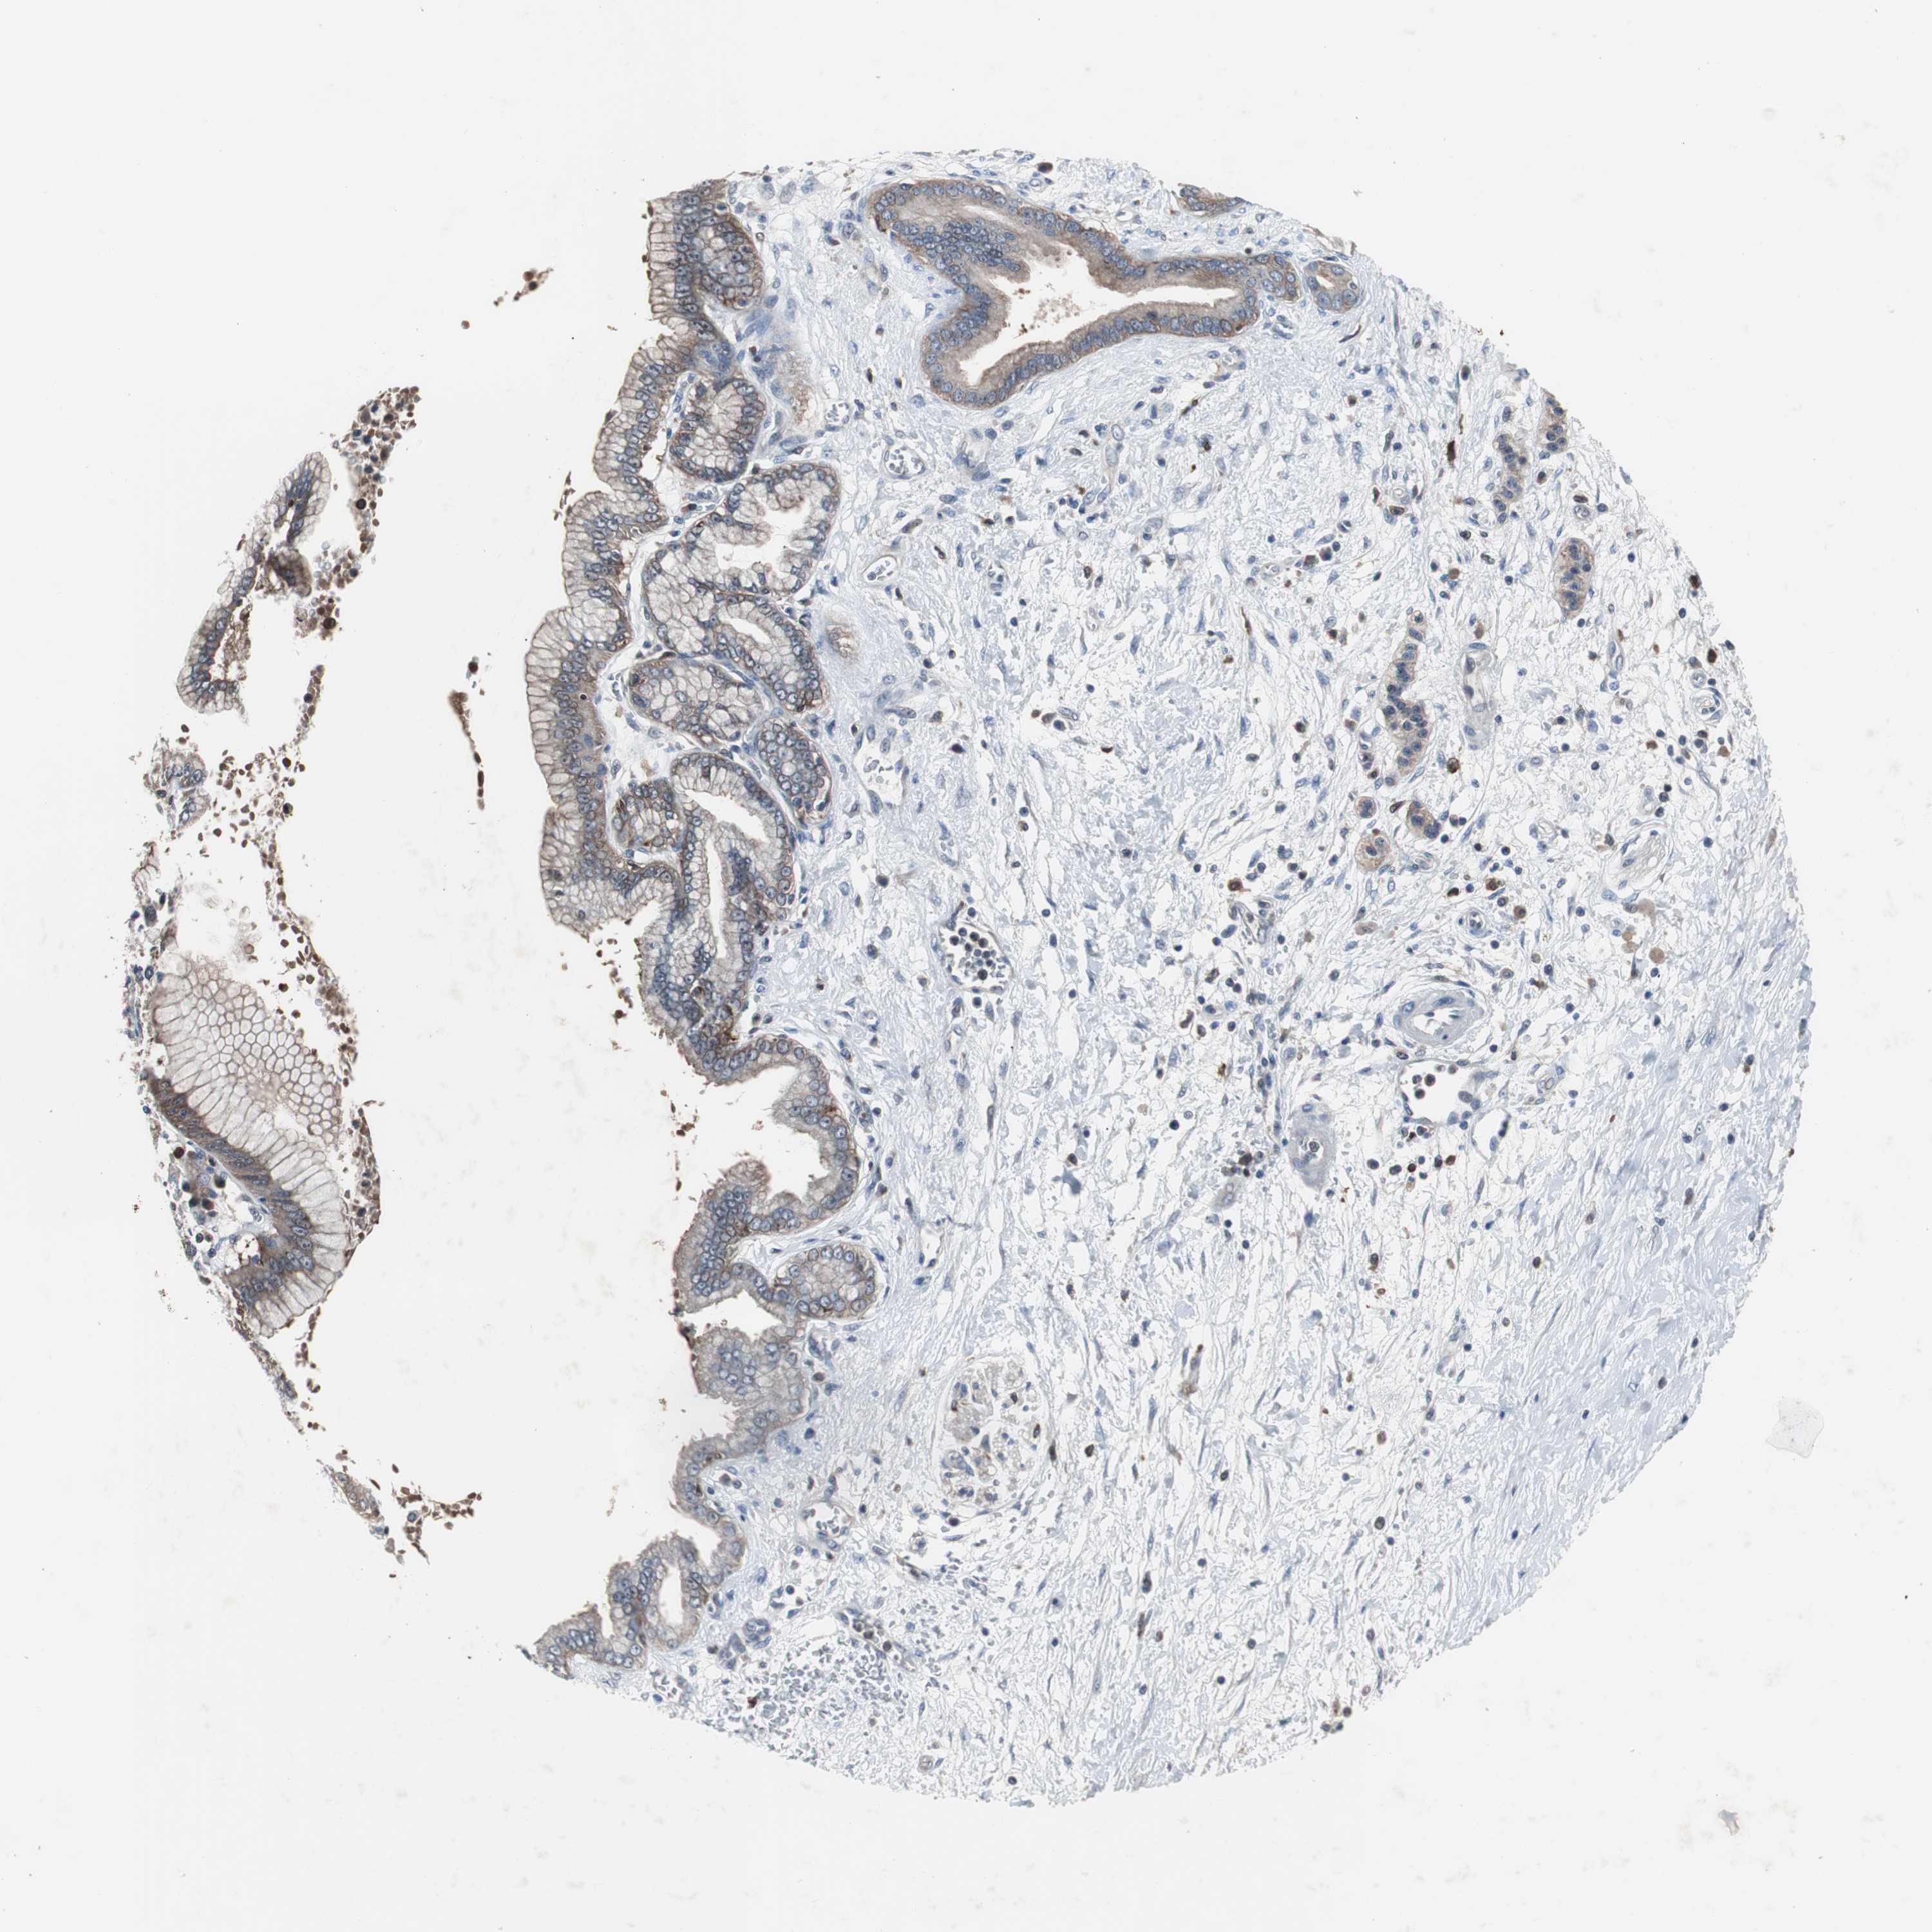

PANCREATIC CANCER - Protein expressioni

A mouse-over function shows sample information and annotation data. Click on an image to view it in a full screen mode. Samples can be filtered based on level of antibody staining by selecting one or several of the following categories: high, medium, low and not detected. The assay and annotation is described here.

Note that samples used for immunohistochemistry by the Human Protein Atlas do not correspond to samples in the TCGA dataset.

Antibody stainingi

Antibody staining in the annotated cell types in the current human tissue is reported as not detected, low, medium, or high, based on conventional immunohistochemistry profiling in selected tissues. This score is based on the combination of the staining intensity and fraction of stained cells.

Each image is clickable and will lead to virtual microscopy that enables deeper exploration of all samples and also displays staining intensity scores, fraction scores and subcellular localization as well as patient and tissue information for each sample.

Antibody HPA003565

Antibody CAB005312

Staining

High

Medium

Low

Not detected

Intensity

Strong

Moderate

Weak

Negative

Quantity

>75%

75%-25%

<25%

None

Location

Nuclear

Cytoplasmic/membranous

Cytoplasmic/membranous,nuclear

Adenocarcinoma, NOS

Adenocarcinoma, metastatic, NOS